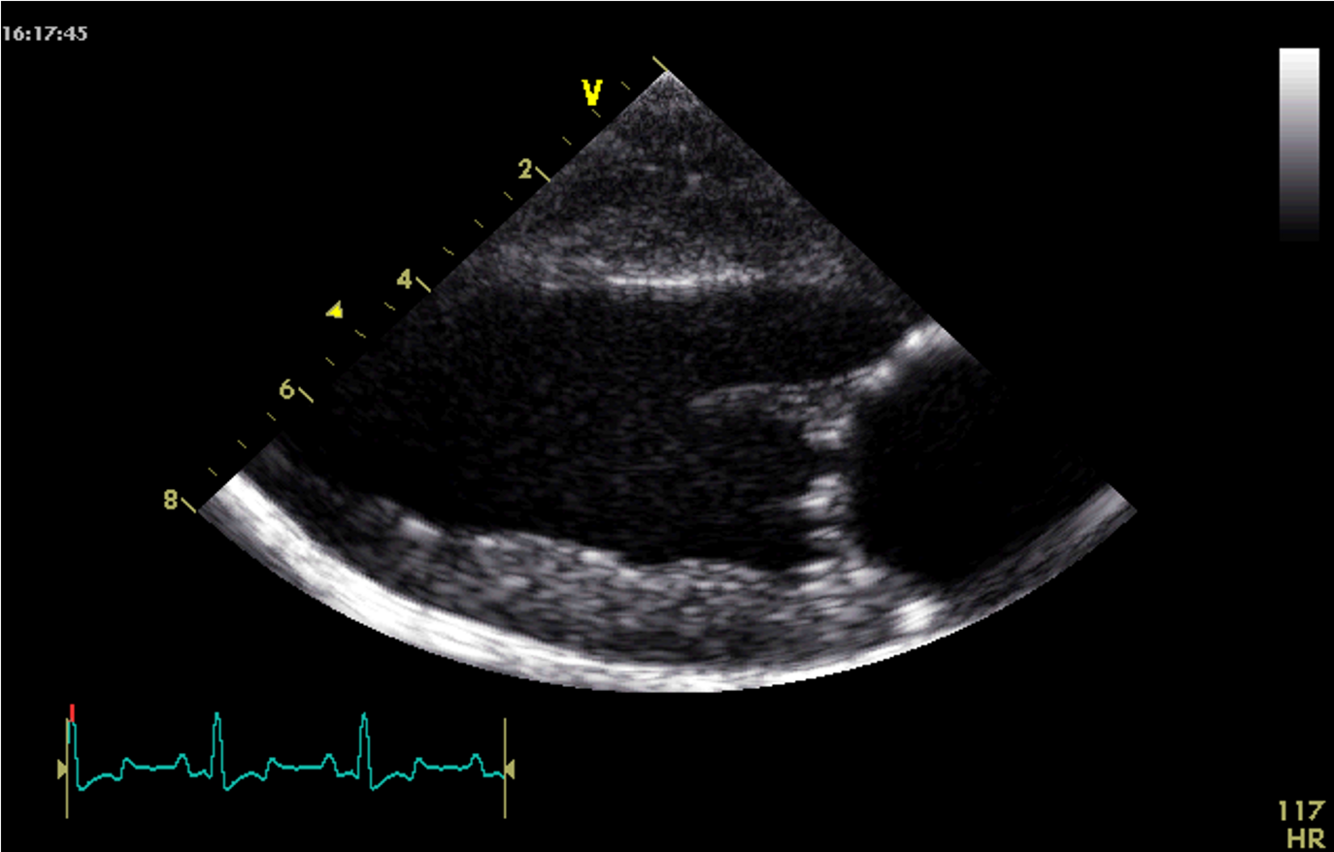

Which view is this?

Right parasternal long axis 4 chamber